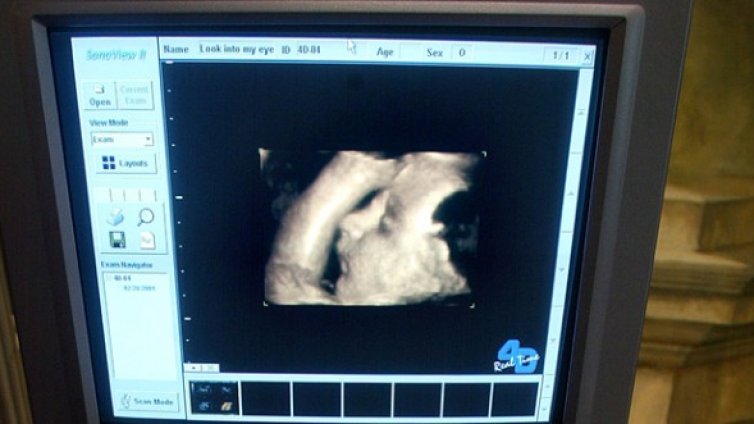

Аборт? Първо чуйте как бие сърцето на бебето